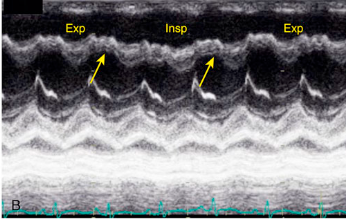

Septal compression toward LV (systole and diastole)

Right ventricular pressure overload

What is the arrow pointing to?

What condition is this finding demonstrated in?

Septal compression toward LV during diastole (normal systole)

Right ventricular volume overload